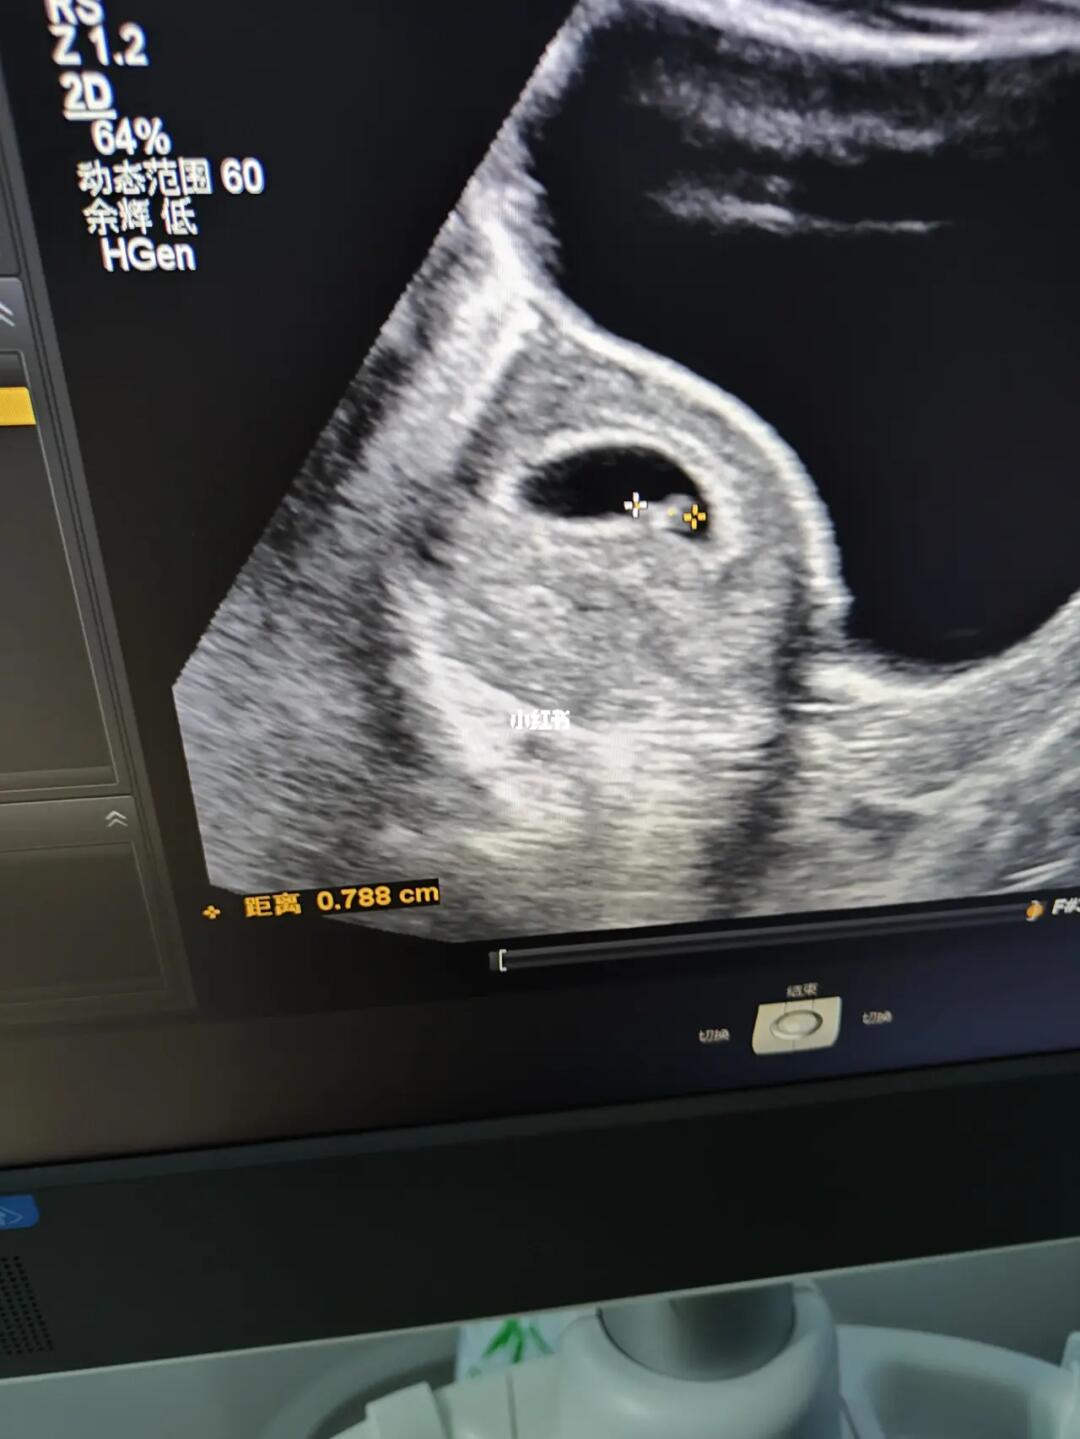

躺了几天 又去做了个b超 孕囊位置上去了 胎心胎芽也有了棒棒的兔